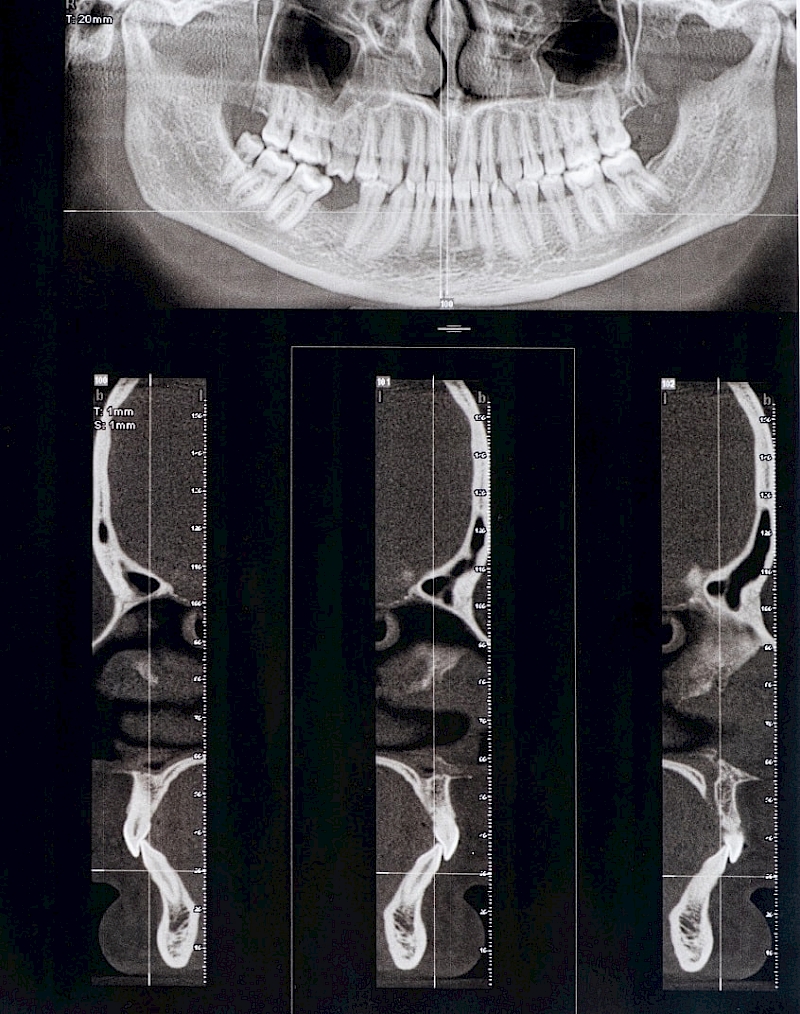

Displacement of the disc or degenerative changes in the condyle and disc may also occur in the TMJ. Differences in clinical symptoms in the TMJ cannot always be explained as disc displacement. The function and dysfunction of the masticatory muscles should also be taken into account.